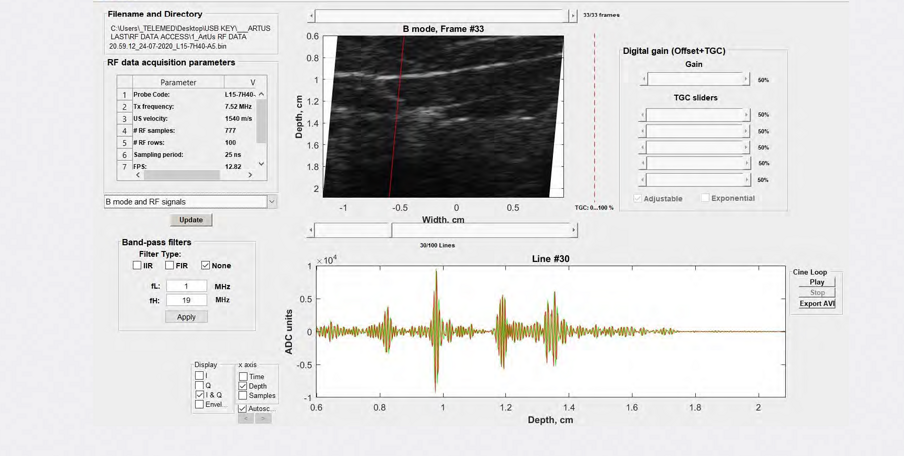

Sistemi diagnostici a ultrasuoni ad architettura aperta per la ricerca